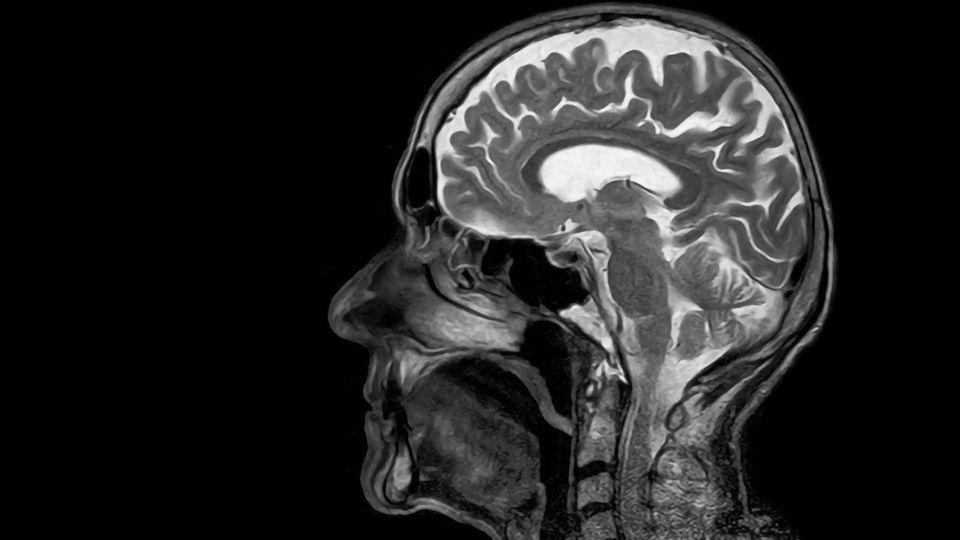

Scientists from Japan and the United States have identified a new mechanism of blood-brain barrier degradation in the post-stroke brain, involving acrolein-induced modifications of proheparanase. This discovery could lead to the production of newer and more effective drugs for stroke-related disorders. Credit: Toubibe from Pixabay